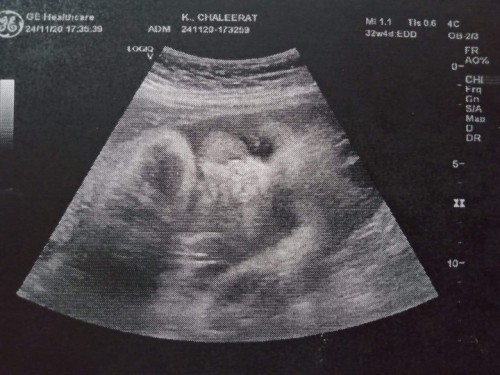

กำลังดูดนิ้วครับ ทีมธันวา☺️☺️